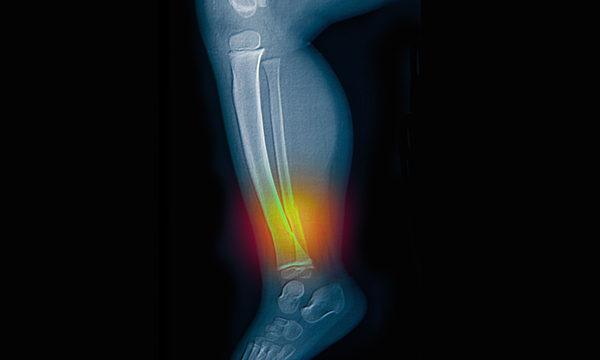

Case study analysis of a two-year-old admitted to the ED in a case of unexplained fractures

This is a summary of the peer-reviewed article: Abdominal X-rays in children: indications, proced